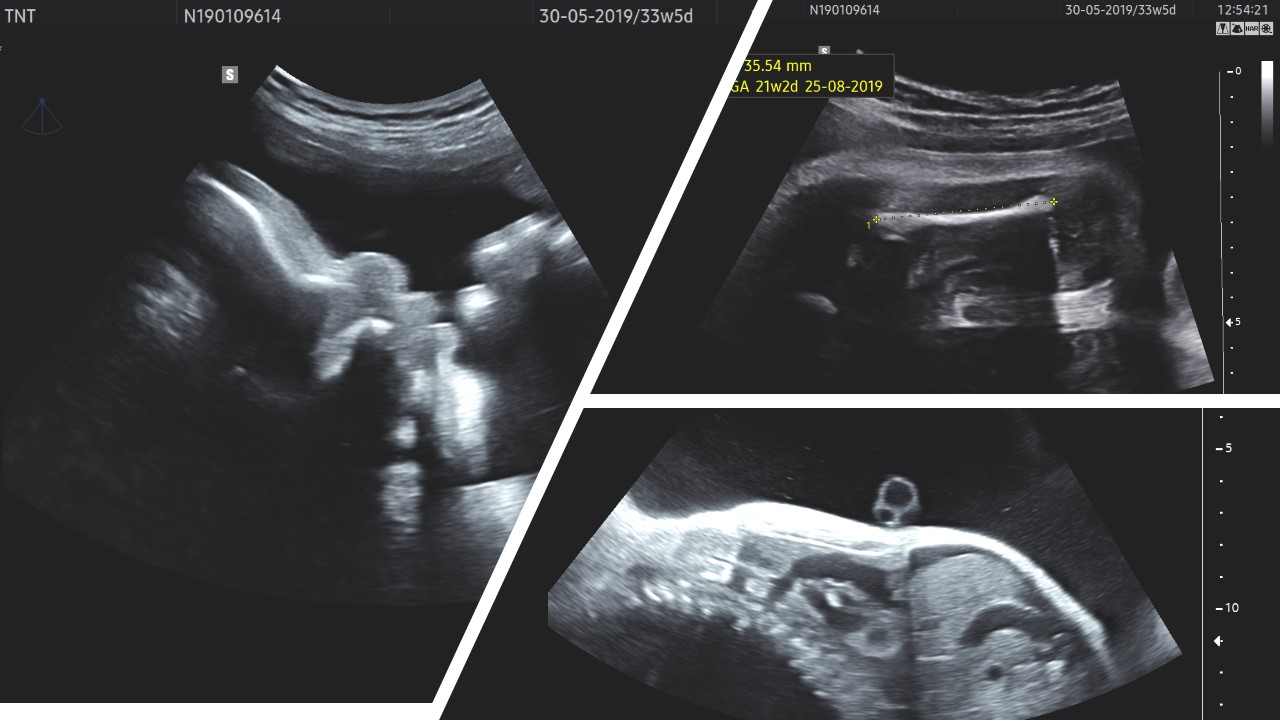

CES - clinical exome sequencing, Tiếp cận mới trong chẩn đoán trước sinh

Trần Nhật Thăng, BM Phụ sản, Khoa Phụ Sản - BV Đại học Y dược TP. HCM